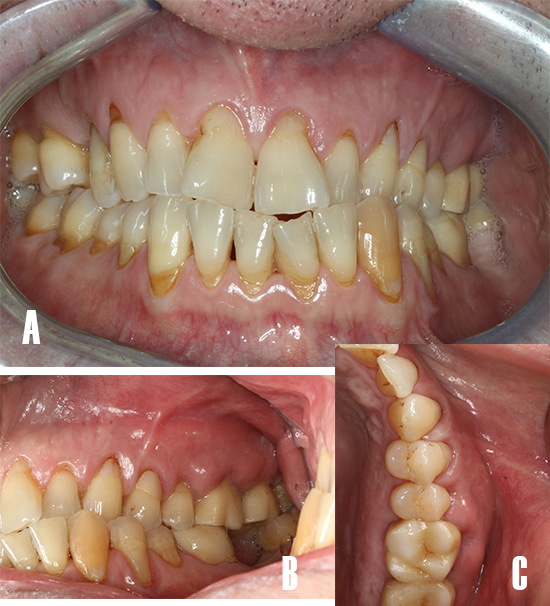

A la exploración clínica se observan recesiones gingivales generalizadas, y restauraciones con resina en la zona cervical de los dientes (Fig. 1A), presenta una restauración ceramo-metálica a nivel de 2.6 y 2.7, los tejidos blandos anexos al diente afecto se observan tumefactos, sin secreciones purulentas ni tracto sinuoso (Fig. 1B).

Figura 1. Fotografía intraoral. A) Vista frontal: nótese las recesiones gingivales generalizadas y restauraciones con resina en cervical de los dientes. B) Imagen lateral: nótese la zona tumefacta a nivel de 26 y 27. C) Vista oclusal: se observa el absceso periodontal tumefacto extendiéndose de distal 25 a media 27.

El molar 2.6 presentaba dolor a la percusión. Tras la evaluación periodontal se observan bolsas periodontales y sangrado al sondaje en la zona mesio-vestibular de 2.7 y 2.8. Los valores medios de pérdida de inserción clínica (2mm), la profundidad de sondaje (1.7 mm), índice de placa (19%) y sangrado al sondaje (9%), nos indican que estamos ante un caso de periodontitis (Estadío I) de complejidad localizada (<30% dientes). El caso periodontal está modificado por la presencia de absceso periodontal/lesión endo-periodontal, recesiones gingivales, fuerzas oclusales traumáticas.